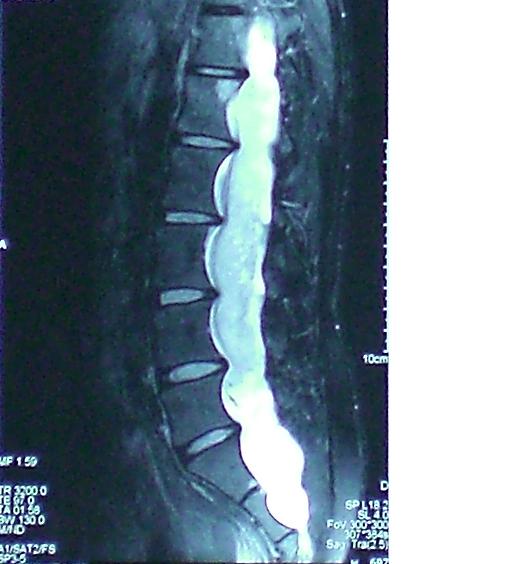

神经外科王振宇主任与马长城教授详细地询问病人的病史,为病人进行了细致的查体后怀疑患者存在脊髓的疾病,而为病人进行了脊髓的核磁检查,结果发现患者椎管内有巨大巨长的肿瘤,肿瘤上端至第五胸椎水平,一直延续到骶管的末端,占据整个椎管,而且由于对脊椎的长期压迫,已经使椎管明显扩大。